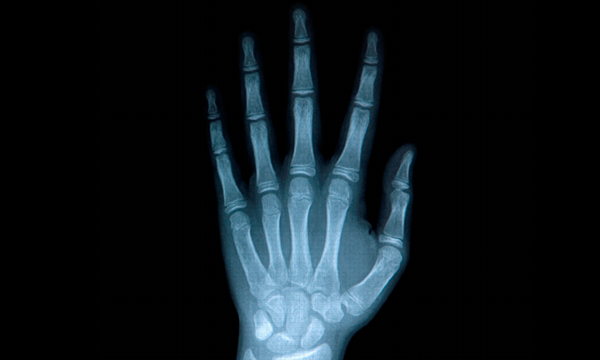

수부란?

손은 손가락 끝에서 손목까지의 부위를 말합니다.

손을 이루는 뼈는 양손을 합치면 총54개로 몸 전체를 이루는 뼈의 1/4가량이 손에 집중되어 있고, 신경, 힘줄, 혈관 등과 함께 섬세한 조화를 이루며 정교한 작업을 수행하는 매우 복잡한 부위 중 하나입니다. 살아가는데 있어서 없어서는 안될 중요한 부위지만 손에 나타나는 증상을 간과하는 경우가 많습니다.